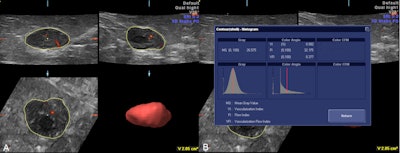

A 36-year-old woman with fibroadenoma. Decreased vascularization was seen in 3D power Doppler ultrasound (A) and also decreased vascular indexes in the histogram (B). Image courtesy of Dr. Ali Kupeli.

Three vascular indexes were obtained in this study using a Voluson 730 Expert, GE Healthcare system: vascularization index, flow index, and vascularization flow index. Vascularization index is the ratio of color voxels to all voxels in the interested volume and shows the density of vessels. Flow index is the mean value of all color voxels in the studied volume and represents average color intensity. Vascularization flow index is the combination of the two and the sum of weighted color voxels divided by all voxels, and it shows vascularization and perfusion.